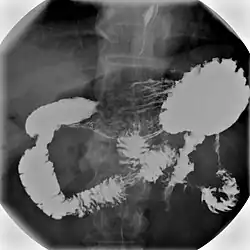

Upper gastrointestinal series

An upper gastrointestinal series, also called a barium swallow, barium study, or barium meal, is a series of radiographs used to examine the gastrointestinal tract for abnormalities. A contrast medium, usually a radiocontrast agent such as barium sulfate mixed with water, is ingested or instilled into the gastrointestinal tract, and X-rays are used to create radiographs of the regions of interest. The barium enhances the visibility of the relevant parts of the gastrointestinal tract by coating the inside wall of the tract and appearing white on the film. This in combination with other plain radiographs allows for the imaging of parts of the upper gastrointestinal tract such as the pharynx, larynx, esophagus, stomach, and small intestine such that the inside wall lining, size, shape, contour, and patency are visible to the examiner. With fluoroscopy, it is also possible to visualize the functional movement of examined organs such as swallowing, peristalsis, or sphincter closure. Depending on the organs to be examined, barium radiographs can be classified into "barium swallow", "barium meal", "barium follow-through", and "enteroclysis" ("small bowel enema"). To further enhance the quality of images, air or gas is sometimes introduced into the gastrointestinal tract in addition to barium, and this procedure is called double-contrast imaging. In this case the gas is referred to as the negative contrast medium. Traditionally the images produced with barium contrast are made with plain-film radiography, but computed tomography is also used in combination with barium contrast, in which case the procedure is called "CT enterography".[1]

Types

Various types of barium X-ray examinations are used to examine different parts of the gastrointestinal tract. These include barium swallow, barium meal, barium follow-through, and barium enema.[2] The barium swallow, barium meal, and barium follow-through are together also called an upper gastrointestinal series (or study), whereas the barium enema is called a lower gastrointestinal series (or study).[3] In upper gastrointestinal series examinations, the barium sulfate is mixed with water and swallowed orally, whereas in the lower gastrointestinal series (barium enema), the barium contrast agent is administered as an enema through a small tube inserted into the rectum.[2]

- Barium swallow X-ray examinations are used to study the pharynx[4] and esophagus.[2]

- Barium meal examinations are used to study the lower esophagus, stomach and duodenum.[2]

- Barium follow-through examinations are used to study the small intestine.[2]